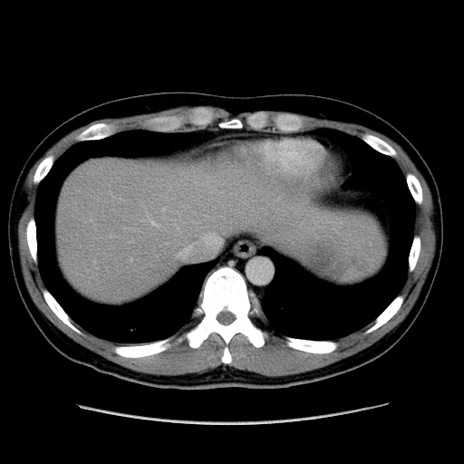

冠状断像

【症例】30歳代男性

【主訴】腹痛、嘔吐

【現病歴】昨晩から突然の腹痛あり、その後嘔吐、軟便も出現。腹痛が改善しないため救急搬送となる。2日前にしめ鯖の食事歴あり。

【身体所見】意識清明、苦悶様、BP 135/90mmHg、BT 35.7℃、腹部:平坦、やや硬、心窩部〜臍部に自発痛、圧痛あり、筋性防御+、反跳痛-

【データ】WBC 8100、CRP 0.57